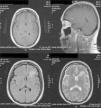

Caso clínicoMujer de 47 años, con diagnóstico de LES hace 10 años, con un brote de actividad renal un año previo a su ingreso, que ameritó tratamiento con micofenolato mofetilo (MMF) 3g al día, prednisona 1mg/kg con reducción hasta 0,5mg/kg/día, lográndose la remisión de la actividad. Ingresó con cefalea de inicio súbito, holocraneana, de intensidad 9 de 10 en la escala visual análoga; se agudizaba con el movimiento y sin mejoría con analgésicos, acompañada de fiebre y náuseas. En la exploración física, sin alteración del estado de consciencia, afectación de funciones mentales superiores o datos neurológicos focales y signos meníngeos negativos. Estudio de líquido cefalorraquídeo (LCR) con leucocitos 27/mm3 (80% mononucleares), eritrocitos 45/mm3, hiperproteinorraquia, normoglucorraquia, tinta china y tinción de Gram, negativas; IgM e IgG para citomegalovirus y herpes virus negativos. Sus estudios de laboratorio mostraron leucocitosis de 13 000 cél./mm3, con neutrofilia y monocitosis, niveles de C3 bajos con C4 normal, elevación de los títulos de anti-ADN, sedimento urinario con proteinuria, eritrocituria y cilindros negativos. Diagnóstico inicial de neuroinfección vs. actividad neuropsiquiátrica; se inició tratamiento empírico con ceftriaxona 2g cada 12h, vancomicina 1g cada 12h, aciclovir 600mg cada 8h, dexametasona 8mg cada 8h. En la resonancia magnética (RMN) cerebral se documentó, a nivel del lóbulo frontal, una lesión compatible con un absceso cerebral (fig. 1). A las 48h, el LCR se reportó incoloro, sin leucocitos, 15 eritrocitos, proteínas 39mg/dl y normoglucorraquia, PCR para M. tuberculosis, negativo. A los 4 días, se reportó crecimiento de LM en el LCR, hemocultivo negativo, cambiando el tratamiento a ampicilina 2g por vía intravenosa cada 4h por 6 semanas, con resolución completa del cuadro clínico sin secuelas. La RMN cerebral al mes mostró un área de impregnación nodular de 3mm de diámetro en situación frontal con mínimo edema adyacente. A los 4 meses, sin evidencia del proceso infeccioso (fig. 2).